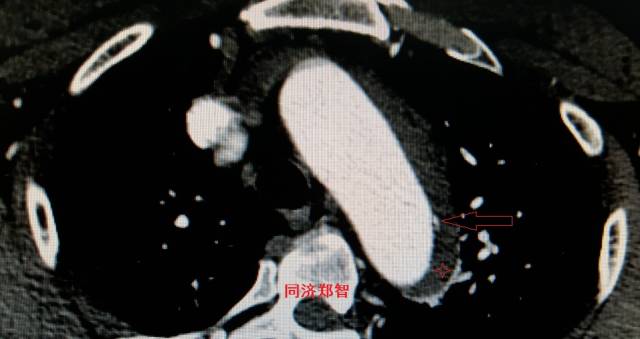

病例五

平扫CT提示主动脉弓层面及右肺动脉层面均可见主动脉血管腔内的内膜片影(红色箭头所示),CTA显示为A型主动脉夹层。